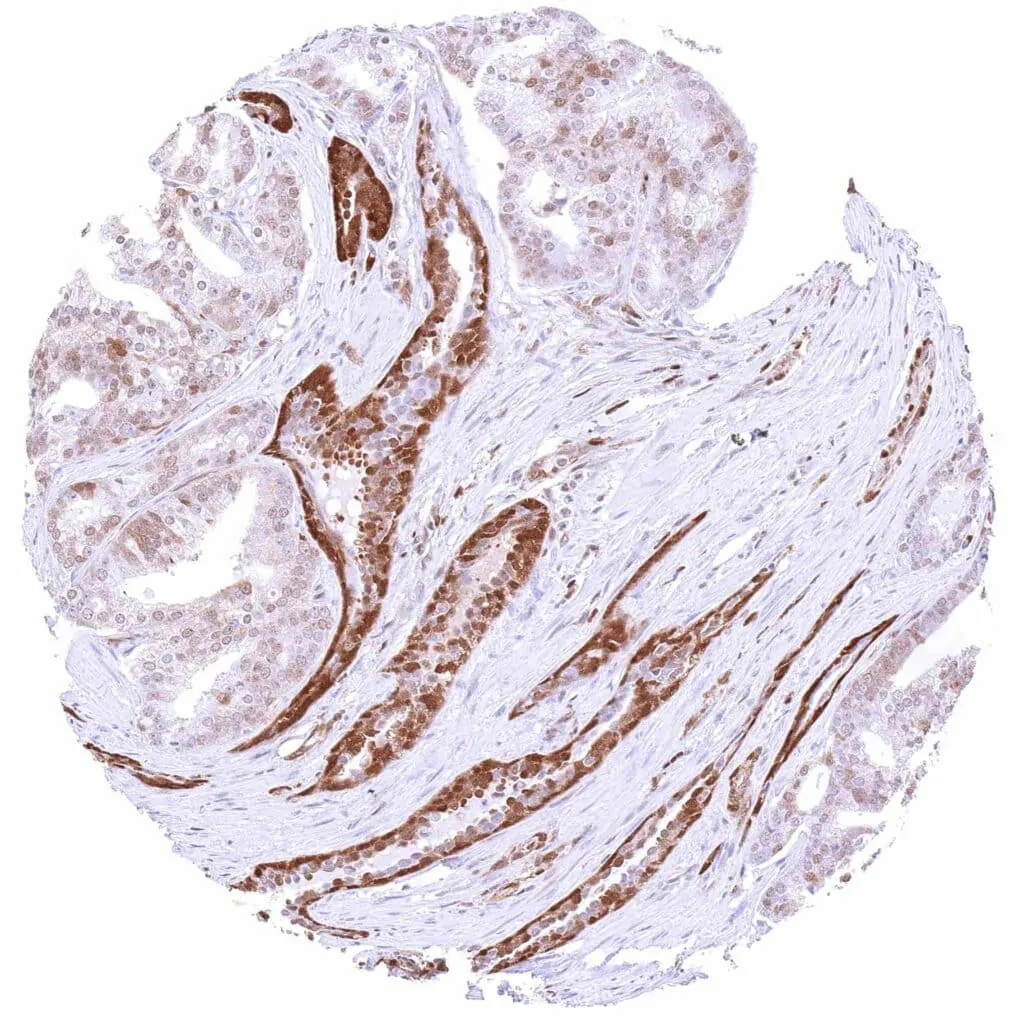

p27 Kip1 antibody [HMV3970] HistoMAX™

Urinary bladder – Muscle-invasive urothelial carcinoma with moderate to strong, predominantly nuclear p27 staining of tumor cells.